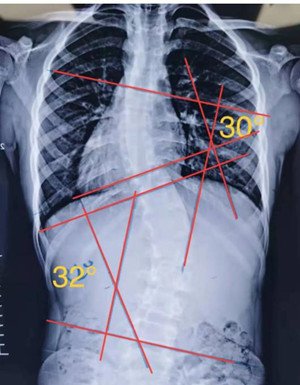

S型側(cè)彎,無(wú)論向哪個(gè)方向側(cè)躺,對(duì)其中一邊的彎度都是不利的,這種情況盡量以平躺為主。